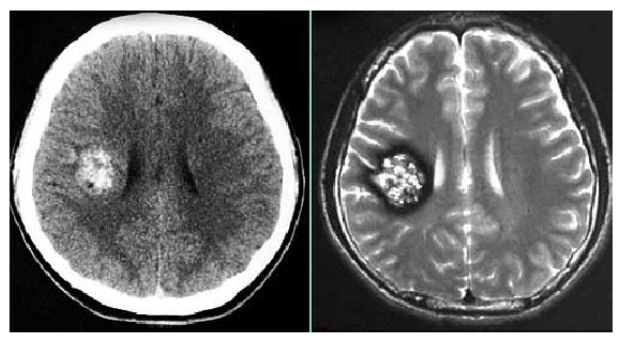

从MRI磁共振T2像特征来看,它确实跟“爆米花”很像。医学上描述其影像表现为:低信号环(陈旧性出血)围绕的混杂信号(不同程度出血呈现出的环瓣)团块。

颅内海绵状血管瘤MRI影像